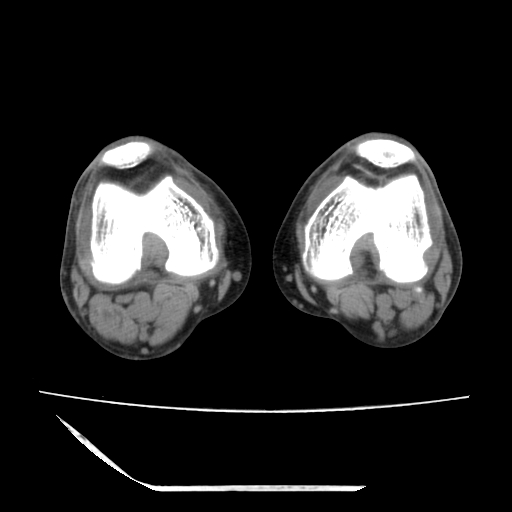

标题: CT13225:老年男性,左膝关节疼痛数月;请各位老师讨论。 [打印本页]

标题: CT13225:老年男性,左膝关节疼痛数月;请各位老师讨论。

骨质增生,骨性关节面硬化,关节积液,考虑退行性骨关节病

关节腔内少量积液,关节面退变。

双膝退变

骨质增生,骨性关节面硬化,关节间隙失常,关节积液,考虑退行性骨关节病.

骨质增生,骨性关节面硬化,关节积液,考虑退行性骨关节病。

这个病例诊断:退行性骨关节炎